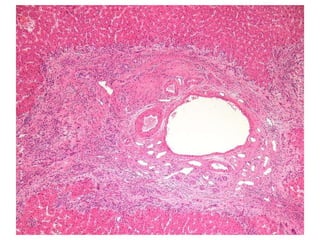

1206/82 54 yo women with Ulcerative Colitis.

LS 1206/82  Dx: Bile duct injury and paucity compatible with primary sclerosing cholangitis Comment: There is focal, marked portal expansion by ductular reactions, inflammatory infiltrates and fibrosis.

1206/82 54 yowomen with Ulcerative Colitis.